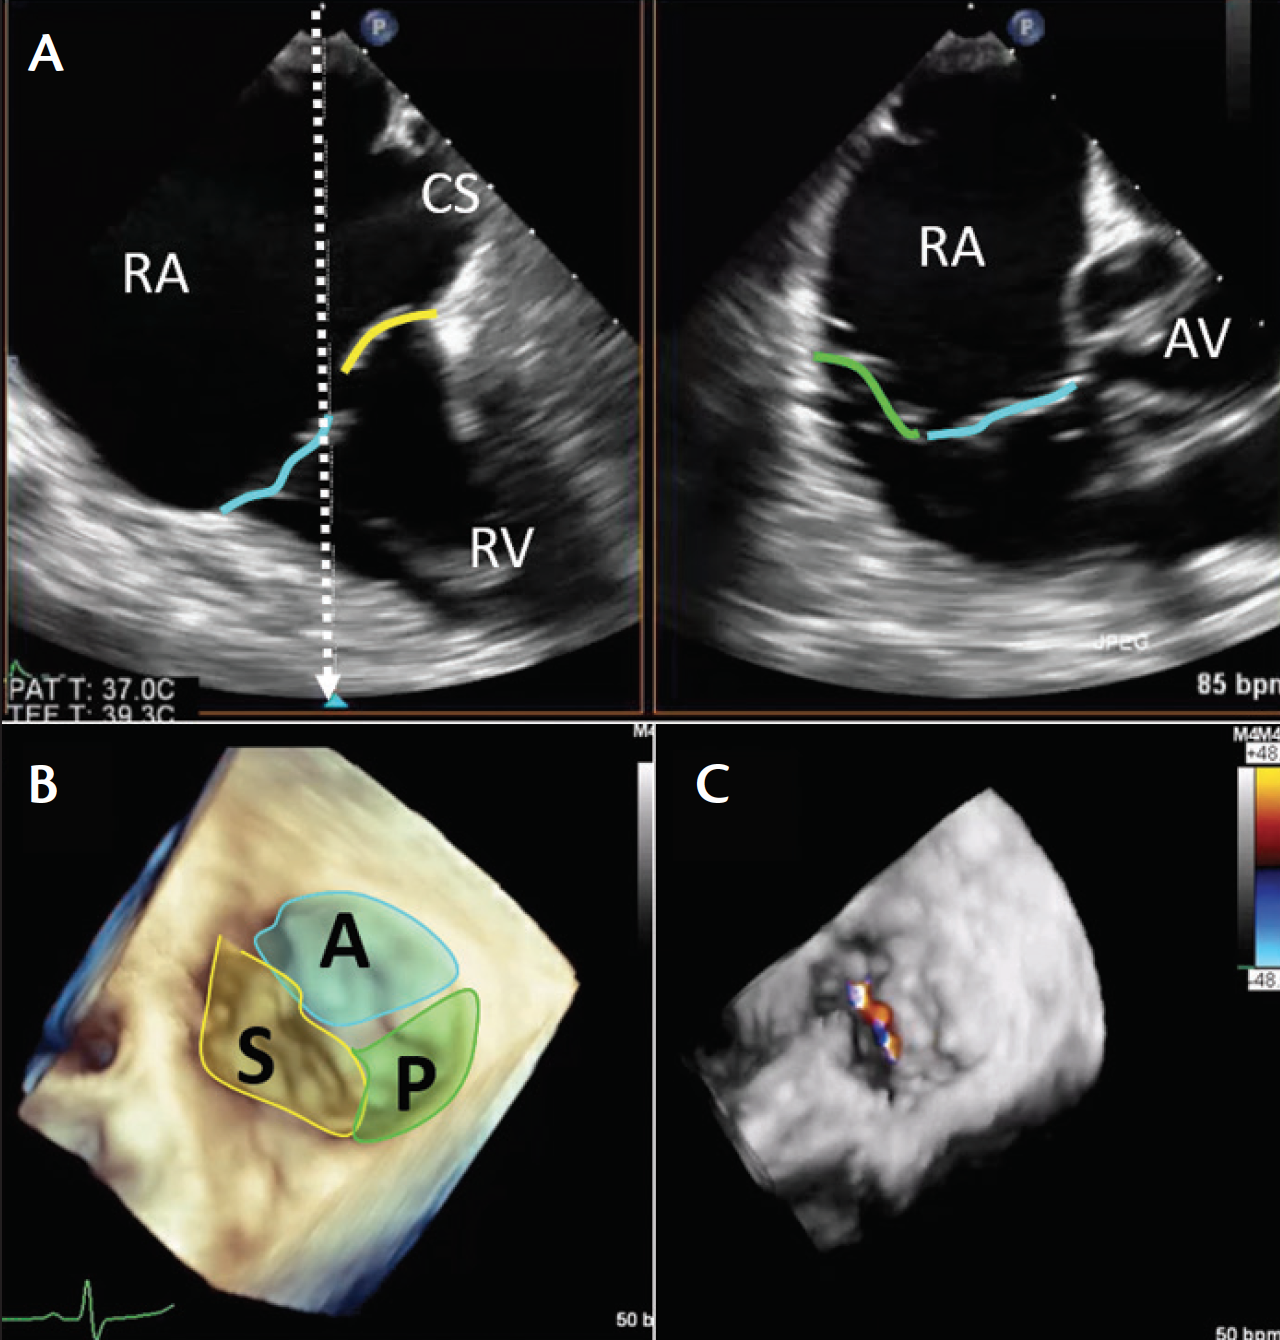

Figure 1. Three-dimensional TEE and CT measurements of the tricuspid annulus. Multiplanar reconstruction of the tricuspid annulus on 3D TEE taken from the deep esophageal view (A). The blue-framed panel shows the annular area and dimension measurements of the tricuspid annulus. Plane of the tricuspid annulus on CT with similar measurements (B).

Given the complex, 3D anatomy of both the tricuspid annulus and right ventricle, it is likely that 3D imaging modalities such as 3D echocardiography, CT scanning (Figure 1), and cardiovascular MRI will replace current measurements, which primarily rely on 2D imaging.69-71 There are some challenges to imaging the right heart. Homogeneous enhancement of the structures around the tricuspid valve annulus may be difficult, with streak artifact arising from high-attenuation superior vena cava contrast enhancement mixing with unenhanced blood of the inferior vena cava. These artifacts may be reduced by a femoral vein injection of contrast or, ideally, simultaneous injections.69,72 Assessing the end-systolic tenting distance and tricuspid annular dimensions, as well as right ventricular volumes and function, is feasible by CT in patients with functional TR.70,73

The midesophageal inflow-outflow view at approximately 60° images the anterior leaflet (adjacent to the aorta) and the opposing posterior leaflet (Figure 3). From this imaging plane, the septal leaflet is typically only imaged using simultaneous biplane views. An orthogonal imaging plane adjacent to the aorta (Figure 3A) will image septal-anterior coaptation. Moving the orthogonal image away from the aorta (Figure 3B) will image the septal-posterior coaptation. Because the lower right heart border is close to the diaphragm, slow insertion brings the TEE probe to the distal esophagus just proximal to the gastroesophageal junction; there may be no view of the left atrium proximal to the tricuspid valve in this imaging plane, only the right atrium and coronary sinus (Figure 4A). As this view of the tricuspid valve is unobstructed by left heart structures, it is ideal for performing a comprehensive evaluation of tricuspid valve function and for acquiring 3D volumes of the tricuspid valve (Figure 4B and Figure 4C).

Figure 4. Deep esophageal views of the tricuspid valve. Simultaneous multiplane image (A) shows the tricuspid leaflets at 0° rotation with the orthogonal inflow-outflow image. From this view, the tricuspid leaflets are well-imaged, and 3D volumes (B) or color Doppler volumes (C) can be obtained. Note: the color code for tricuspid leaflets is the same as in Figure 2. Abbreviations: A, anterior leaflet; AV, aortic valve; CS, coronary sinus; P, posterior leaflet; RA, right atrium; RV, right ventricle; S, septal leaflet.